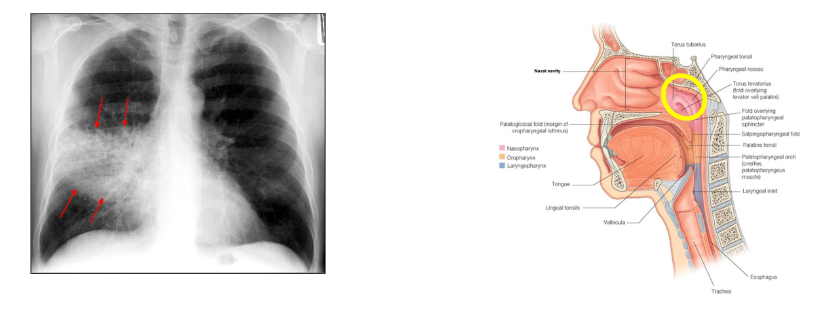

- Lung abscess

- Brain abscess (means swelling due to pus)

- Disseminated infection - bacteraemia

- S. aureus circulating in the bloodstream

- May progress to infection of a heart valve: endocarditis